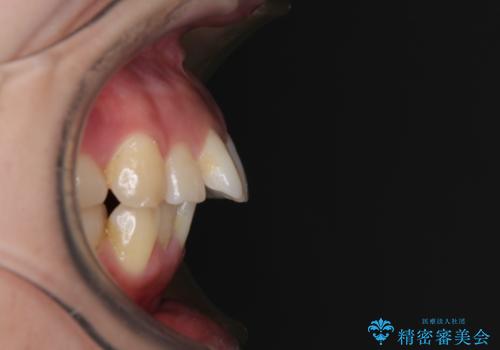

- 前歯のデコボコと口元の突出感を気にして来院された患者様です。

上下前歯がくちばしのように突出していたため、上下左右の第一小臼歯4本を抜歯し、ワイヤー装置にて矯正治療を行うこととしました。